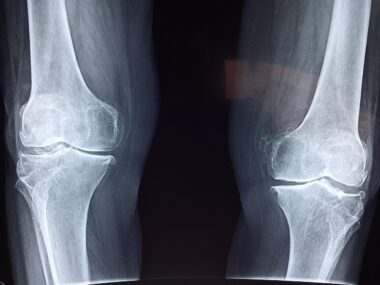

Ongoing pain that doesn’t improve with rest should be considered a red flag. If you’ve been experiencing joint discomfort during everyday activities or exercise, this might suggest the need for expert attention. Remember, joint pain can be a sign of underlying issues that require attention. Persistent pain can severely limit your ability to perform daily tasks, affecting overall quality of life. Whether the pain is sharp or dull, localized or spreading, it is essential to have it professionally evaluated. Relying on over-the-counter pain medications may provide only temporary relief but does not address possible underlying causes. Ignoring prolonged pain might lead to greater complications such as arthritis, tendonitis, or other joint conditions. A sports medicine specialist can provide a comprehensive assessment to identify specific joint problems. This assessment often includes physical examinations, imaging tests like MRIs or X-rays, and personalized treatment strategies. Timely intervention may significantly enhance your recovery process and minimize pain, restoring mobility. Look for specialized clinics that focus on sports injuries and joint health to ensure you receive the highest level of care.